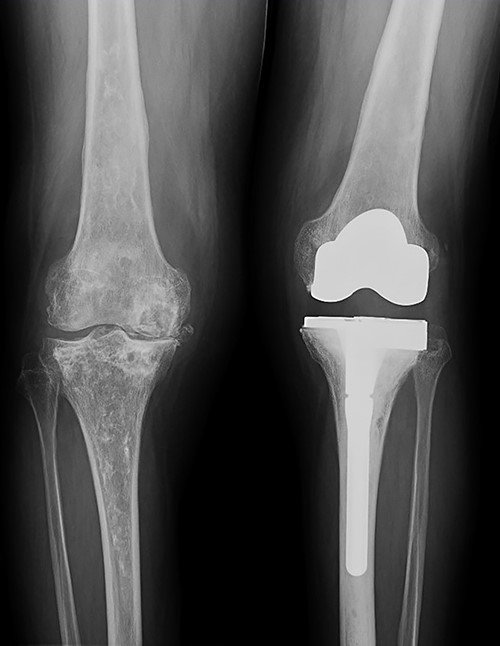

Due to the poor bone quality and defect associated to osteonecrosis (Fig. 3), osteosynthesis was discarded and total knee arthroplasty (TKA) was performed with lateral tibial block and diaphyseal stem (Fig. 4). Microbiological samples confirmed the absence of infection. Pathological samples confirmed osteolysis and chronic synovitis with osteoporosis and osteonecrosis, leading to the pathological fracture (Figs 5 and 6).

X-ray of the left knee showing reconstruction with 10-mm tibial lateral block and a tibial diaphyseal stem.